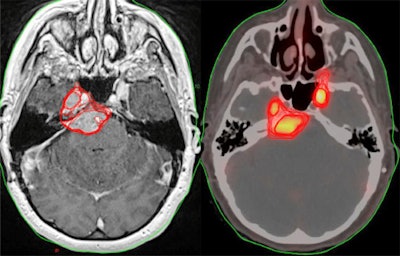

A U.S. group compared Ga-68 DOTATATE PET/CT and contrast-enhanced MRI approaches for treatment planning in patients with meningiomas. They found that clinicians identified additional areas of disease on PET compared with MRI alone.

The current standard of care for meningiomas includes MR-based imaging to define the tumors, followed by radiation therapy. PET imaging with Ga-68 DOTATATE, a radiotracer that binds to meningioma cancer cells, has shown better performance than MRI at defining gross tumor volume, but the practice has not been widely adopted.

Four radiation oncologists and three neuroradiologists were instructed to contour visible tumors on both scans to create gross tumor volumes, which were then compared. Gross tumor volumes have important implications when clinicians determine radiotherapy doses, since controlling tumors requires higher doses if the tumor cell numbers are larger.